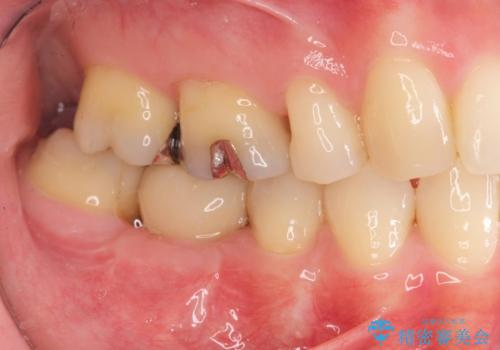

- 歯の破折により失ってしまった右下の歯の機能回復を求めて来院されました。

取り外しの必要な入れ歯や、歯を大きく削る必要のあるブリッジではなく、インプラント治療を希望されました。

骨の増成を含むインプラント治療を計画します。